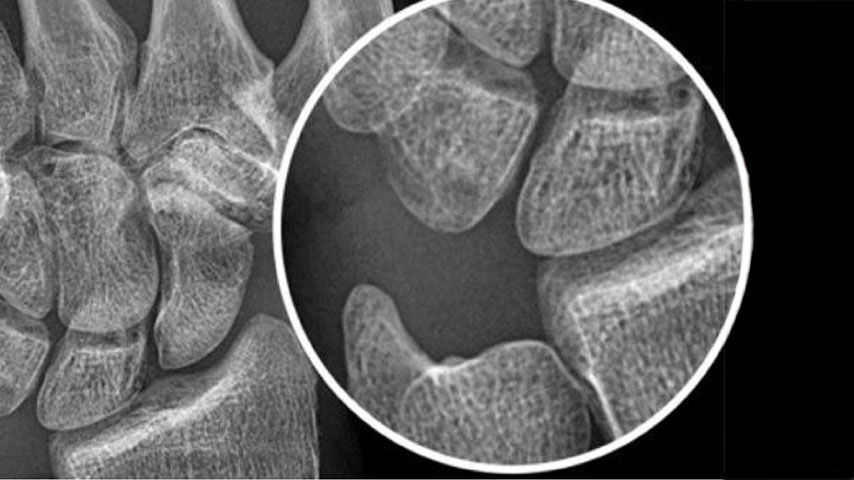

Advanced applications and IQ

Enable radiologists to consistently see more details and provide quality diagnosis